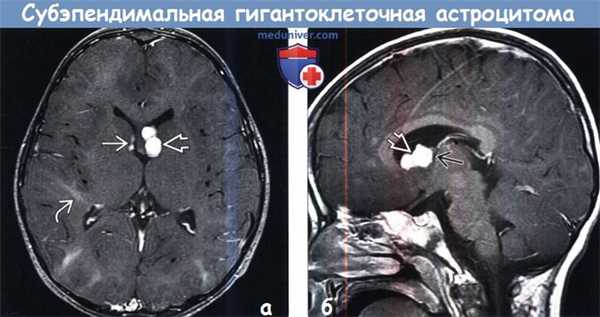

(а) МРТ, Т1-ВИ, аксиальный срез: у мальчика 13 лет с ТС по ходу переднего рога правого бокового желудочка определяются 2 СЭУ.

Кроме того, в переднем роге левого бокового желудочка, прилегая к отверстию Монро, визуализируется двудольчатое объемное образование со смешанной интенсивностью сигнала.

Обратите внимание на кортикальные туберсы, нечеткость границ между серым и белым веществом.

(б) MPT, Т1 -ВИ, более краниальный аксиальный срез: у того же пациента определяются другие СЭУ.

(а) МРТ, Т2-ВИ, аксиальный срез: у того же пациента в левом переднем роге определяется образование дольчатой структуры гиперинтенсивного по отношению как к белому, так и к серому веществу сигнала.

В структуре субкортикального белого вещества под кортикальными туберсами наблюдаются несколько зон гиперинтесивного сигнала в форме «языков пламени».

(б) MPT, FLAIR, аксиальный срез: у того же пациента определяется, что образование дольчатой структуры, расположенное в области переднего рога левого бокового желудочка, не обтурирует боковой желудочек.

Зоны гиперинтесивного сигнала в форме «языков пламени» в структуре белого вещества (БВ) под кортикальными туберсами на данной последовательности визуализируются лучше.

(а) МРТ, постконтрастное T1BИ, режим подавления сигнала от жира: у того же пациента определяется контрастирование СЭУ в области переднего рога правого бокового желудочка, а также контрастирование образования дольчатой структуры в области переднего рога левого бокового желудочка.

Зоны гиперинтесивного сигнала в форме «языков пламени» в структуре БВ на данном изображении видны лучше. Визуализируется один радиальный пучок, простирающийся до границы бокового желудочка.

(б) МРТ, постконтрастное Т1-ВИ, сагиттальный срез: у того же пациента образование левого переднего рога с дольчатой структурой напрямую прилежит к отверстию Монро, но не обтурирует его.

Предполагаемая СГКА у данного пациента наблюдается без хирургического вмешательства и остается стабильной уже в течение нескольких лет.